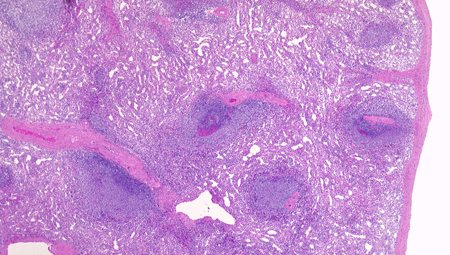

脾臓の組織所見

赤脾髄の構造 Structure of the red pulp

splenicsinus04.png

spleenRp03b.png

脾臓を灌流固定で赤血球を除いています。

左図:赤脾髄の拡大像 1. 脾洞 2.脾索が見えます。

右図:赤血球の残った部分です。脾洞に入り込む赤血球が見えます。

クリックすると大きな画像が見られます。